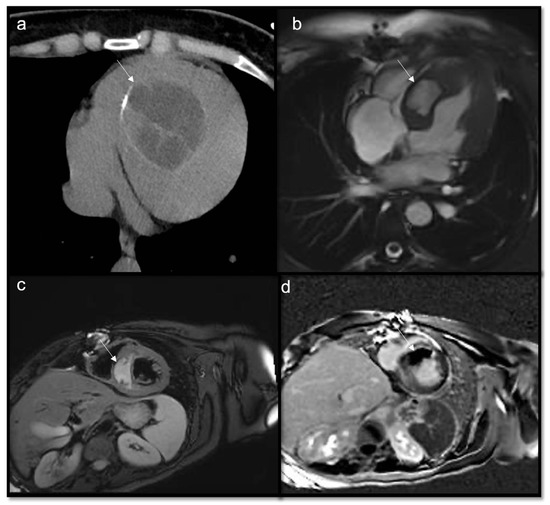

- Malignant masses often show heterogeneous enhancement; typically, angiosarcoma shows early avid enhancement as it is richly vascularized.